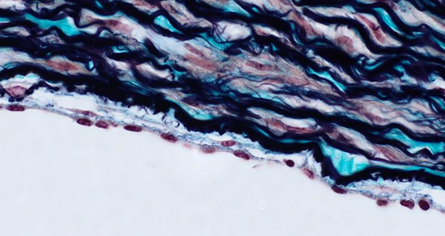

A 67-year-old homeless man is brought

to the emergency department by ambulance. He was found unresponsive by the

police. Despite appropriate first aid and immediate transport to the

hospital, he dies. Examination of the heart during autopsy shows normal size

and shape. A photomicrograph of a section of the heart obtained at

autopsy is shown. How does the amount of substance indicated by the arrow

relate to the person´s age?